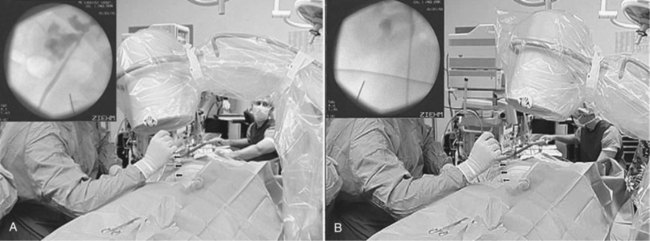

Using a hand-held 3.5- or 5-MHz ultrasound transducer, inspect the kidney and select a calyx for percutaneous entry. Needle guides can be placed on the transducer to direct the needle in the plane of visualization of the probe. Some prefer to place the needle freehand instead, moving the transducer around to gain different views of the kidney and needle. Observe the needle as it is advanced until it appears that the tip is within the collecting system (Fig. 47–17). Removing the obturator and aspirating urine confirms entry.